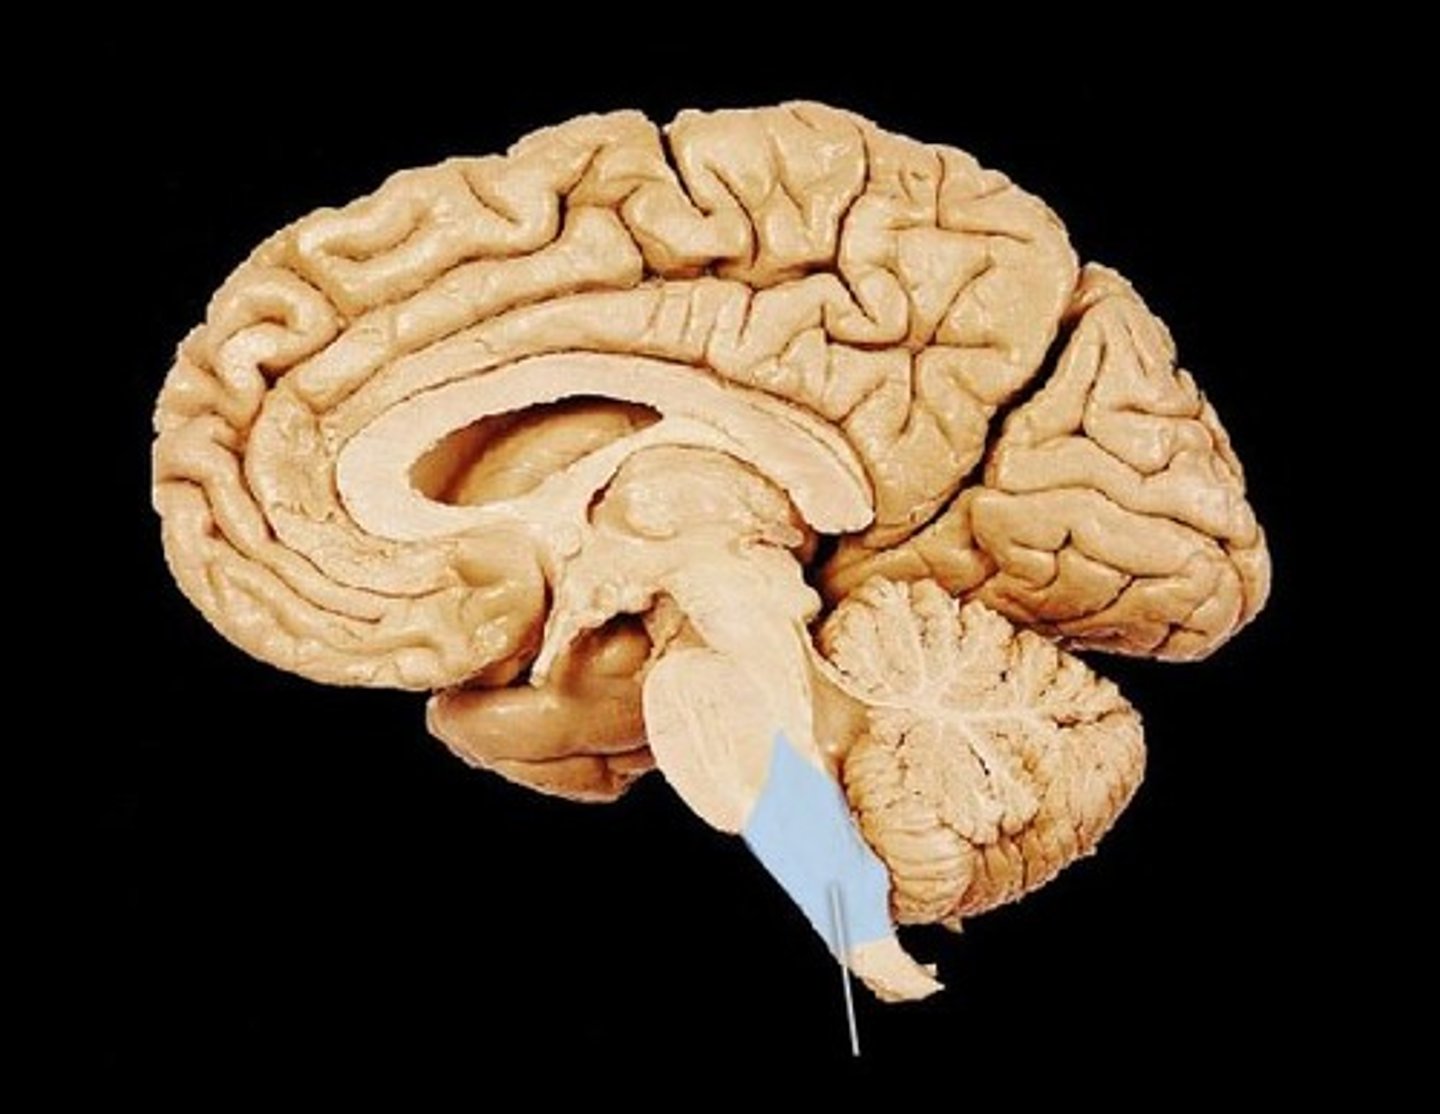

brain stem

continuous with the spinal cord and consists of the medulla oblongata, pons, and midbrain

Cerebellum

posterior part of the brain that coordinates muscle movements and maintains balance

Cerebrum (telencephalon)

supported on diencephalon and brain stem

pons

center structure of the brain stem, located between the midbrain and the medulla oblongata

midbrain

or mesencephalon extends from pons to diencephalon. the pons is the center structure of the brain stem, located between the midbrain and the medulla oblongata

corpus callosum

broad band of white matter containing axons that extend between the cerebral hemispheres